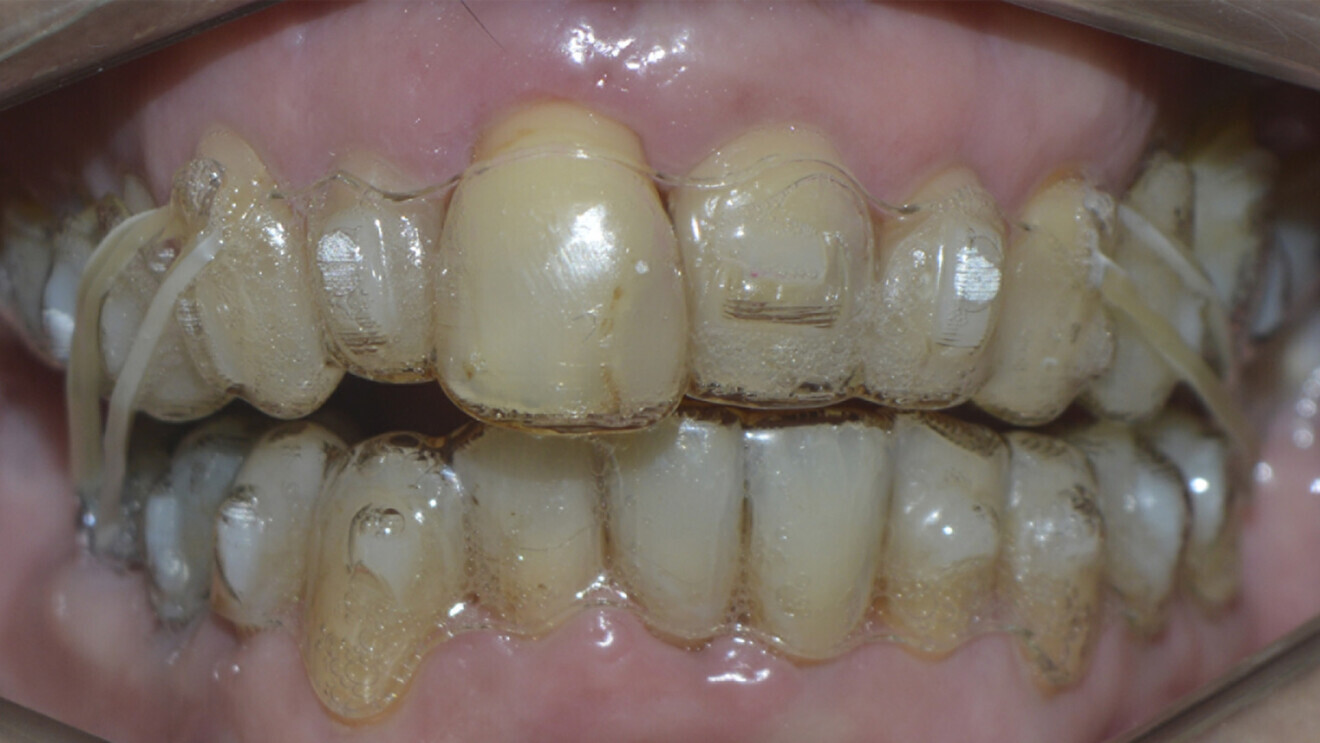

Fig. 8: After periodontal treatment.

Fig. 9: Treatment with aligners.